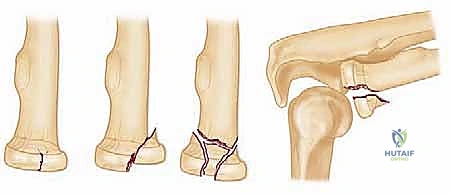

| النوع الأول (Type I) | كسر غير متحرك (Nondisplaced)، أو تحرك أقل من 2 ملم. لا يوجد إعاقة ميكانيكية لحركة الدوران. | علاج تحفظي: أدوية مسكنة، تعليقة للذراع (Sling) لأيام قليلة، ثم بدء العلاج الطبيعي المبكر جداً لمنع التيبس. |

| النوع الثاني (Type II) | كسر متحرك (Displaced) بأكثر من 2 ملم، أو يشمل أكثر من 30% من سطح المفصل. قد يسبب إعاقة في الحركة. | علاج جراحي أو تحفظي: يعتمد على درجة الإعاقة. الجراحة المفضلة هي التثبيت الداخلي (ORIF) بمسامير صغيرة. |

| النوع الثالث (Type III) | كسر مفتت بالكامل (Comminuted). رأس الكعبرة مهشم إلى عدة قطع لا يمكن تجميعها. | علاج جراحي حتمي: إما محاولة التثبيت الدقيق، أو استبدال رأس الكعبرة بمفصل صناعي (Arthroplasty). |

| النوع الرابع (Type IV) | كسر في رأس الكعبرة مصحوب بخلع كامل في مفصل المرفق وتمزق في الأربطة. | علاج جراحي طارئ ومعقد: إصلاح الأربطة، تثبيت أو استبدال رأس الكعبرة، وإعادة الاستقرار للمفصل. |